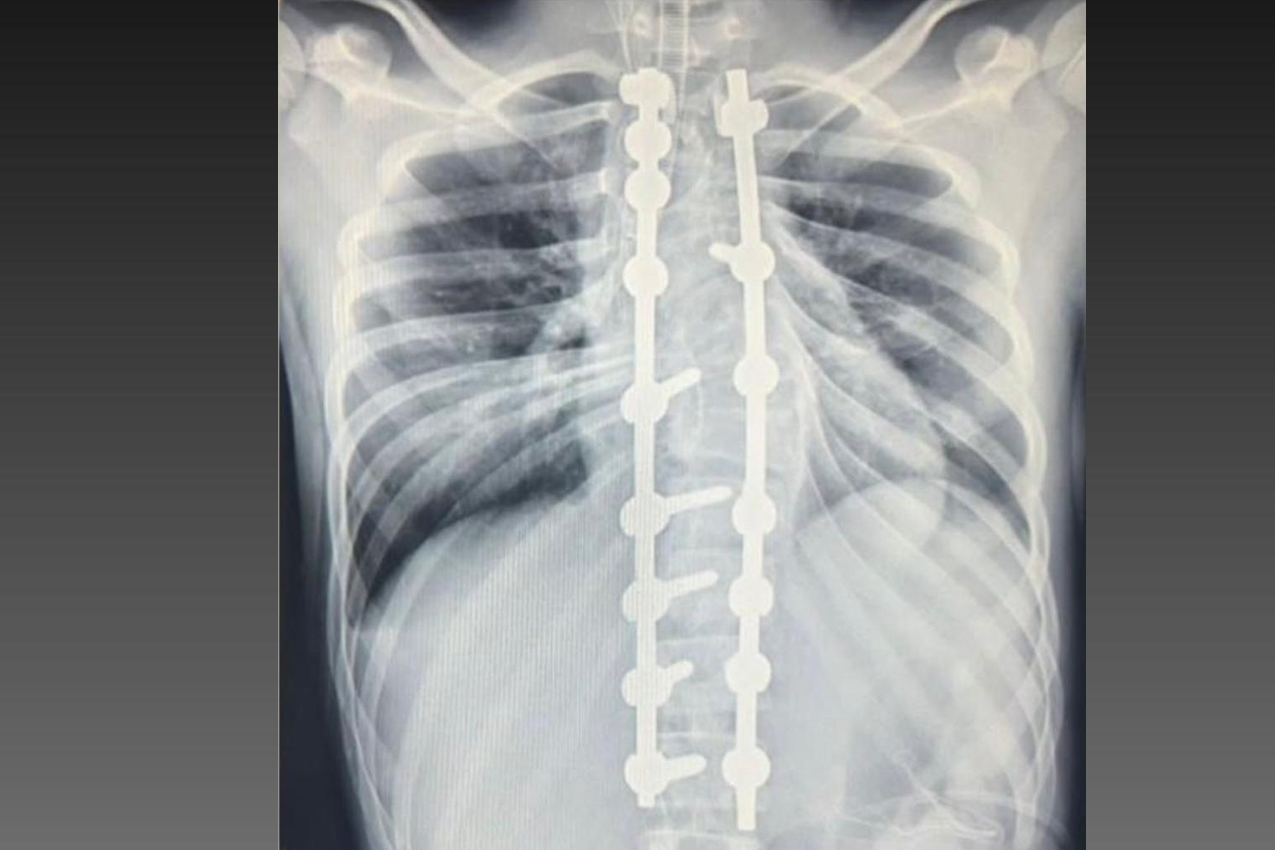

Laura era portadora de escoliose e, em agosto de 2025, realizou a cirurgia de correção da coluna, o que lhe permitirá ter uma vida normal de agora em diante. Moradora de Bom Sucesso do Sul, região Oeste do Paraná, é acostumada a andar a cavalo, mas com o problema na coluna a prática estava longe de ser prazerosa.

“Qualquer coisa que eu fazia, sentia dor. Tomava remédio e parecia que não fazia muito efeito”, contou Laura. “Quando fui fazer a cirurgia, disse que não queria fazer. Hoje, eu me arrependo de ter falado, porque é uma conquista para mim, consegui ajeitar minha coluna. Estou muito realizada, fiquei até alguns centímetros mais alta e consigo fazer tudo o que eu queria”, completou.

“O projeto iniciado em 2023 aqui no CHT já atendeu um grande número de pacientes. Hoje, são poucos os locais de referência para atendimento desses pacientes e temos toda essa estrutura aqui no Paraná. Foram mais de 200 casos operados e centenas de pacientes tratados. Tratamento que vai desde os conservadores, como exercício e fisioterapia, até o uso de coletes gessados e de polipropileno e casos cirúrgicos”.

DIAGNÓSTICO - A escoliose pode ter diferentes causas, sendo classificada em idiopática (sem causa definida), sindrômica (associadas a síndromes genéticas), neuromuscular (decorrente de doenças como paralisia cerebral e atrofia muscular espinhal) e congênita (presente desde o nascimento). Em todos os casos, o diagnóstico precoce e o acompanhamento especializado são fundamentais para determinar a melhor abordagem terapêutica.

O médico João Elias explica que a escoliose é um termo usado para quando você olha a coluna e percebe uma curvatura. Pode acontecer por várias causas, desde uma escoliose congênita, quando o bebê nasce com uma vértebra mal formada e essa vértebra vai levando ao desenvolvimento de uma deformidade na coluna; a neuromuscular, causadas por doenças neurológicas ou musculares, como uma paralisia cerebral, até as idiopáticas, causadas por alterações genéticas e que podem se desenvolver apenas na adolescência.